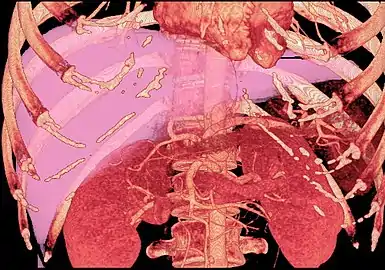

CT scan showing an adult liver in the axial plane

Organogenesis, the development of the organs, takes place from the third to the eighth week during embryogenesis. The origins of the liver lie in both the ventral portion of the foregut endoderm (endoderm being one of the three embryonic germ layers) and the constituents of the adjacent septum transversum mesenchyme. In the human embryo, the hepatic diverticulum is the tube of endoderm that extends out from the foregut into the surrounding mesenchyme. The mesenchyme of septum transversum induces this endoderm to proliferate, to branch, and to form the glandular epithelium of the liver. A portion of the hepatic diverticulum (that region closest to the digestive tube) continues to function as the drainage duct of the liver, and a branch from this duct produces the gallbladder.[35] Besides signals from the septum transversum mesenchyme, fibroblast growth factor from the developing heart also contributes to hepatic competence, along with retinoic acid emanating from the lateral plate mesoderm. The hepatic endodermal cells undergo a morphological transition from columnar to pseudostratified resulting in thickening into the early liver bud. Their expansion forms a population of the bipotential hepatoblasts.[36] Hepatic stellate cells are derived from mesenchyme.[37]